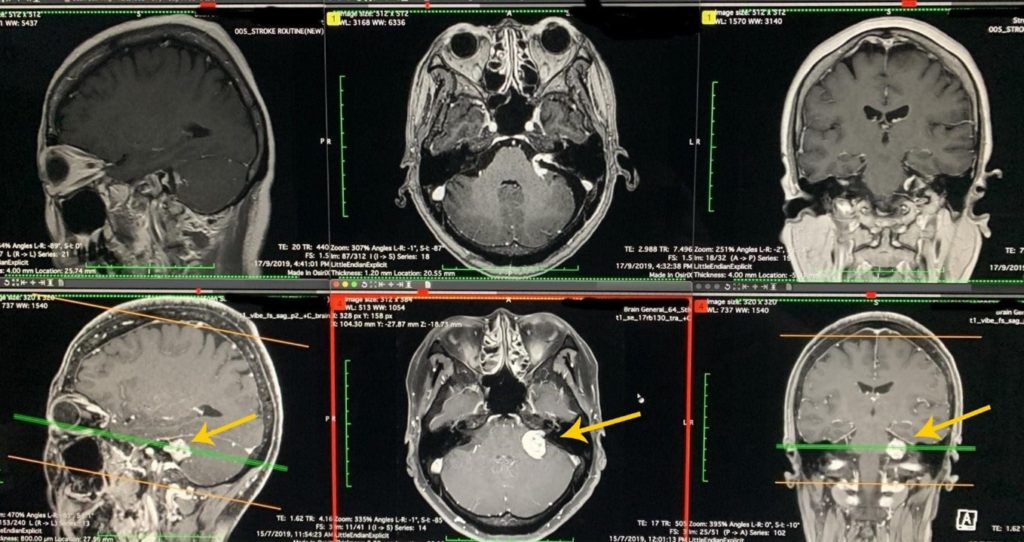

Ms. Zhang, a 46-year-old lady, sought medical treatment accompanied by her daughter. The left tinnitus that bother her for three months, of which symptoms are different from the ordinary tinnitus, was synchronized with the pulse of her heart. Clinical examination showed that doctors could use the stethoscope on Ms. Zhang’s left head and neck to hear a murmur synchronized with the heartbeat pulse, which is typical of vascular tinnitus caused by the overlapping of arteriovenous malformations. After MRI angiography, Ms. Zhang underwent a two-hour minimally invasive pinhole cerebral vascular catheter surgery.

Cerebrovascular surgeons use tiny titanium wire coils to block the overlapping alternation of abnormal sinuses and cerebral artery vessels near Ms. Zhang’s left ear to block the abnormal arteriovenous blood flow, thereby eliminating tinnitus. After the surgery, Ms. Zhang was happily discharged home, accompanied by her daughter. In addition to tinnitus, doctors say that the risk of hemorrhagic stroke caused by abnormal arteriovenous malformations is also relieved.